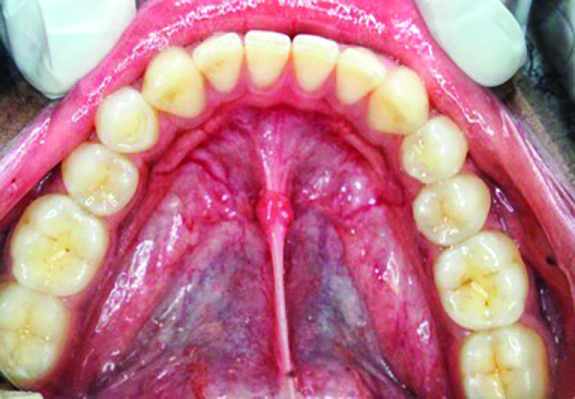

Fig 4 through Fig 6. Lingual attached gingiva in a male subject: Fig 4 = left side.

Figure 4

Fig 5 = middle.

Figure 5

Fig 6 = right side.

Figure 6